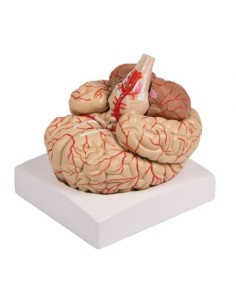

Scopri il Mondo dell’Anatomia con Modelli anatomici di Precisione

Benvenuto su Tuttoanatomia.it, il portale di riferimento in Italia per l’acquisto di modelli anatomici, poster, lettini portatili, simulatori medici e letteratura specialistica. Con i nostri modelli anatomici di 3B Scientific ed Erler Zimmer, leader mondiali nel settore, offriamo un’esperienza di apprendimento senza pari.

Modelli Anatomici Dettagliati per Ogni Necessità

Dal cranio in 22 parti con incastri magnetici ai modelli di colonna vertebrale, da quelli di articolazioni a quelli di cuore, ogni pezzo della nostra collezione è progettato per un’immersione totale nello studio dell’anatomia umana. I nostri modelli, realizzati tramite scansioni di ossa vere, garantiscono un’esperienza tattile autentica e una fedeltà di peso quasi identica agli originali.